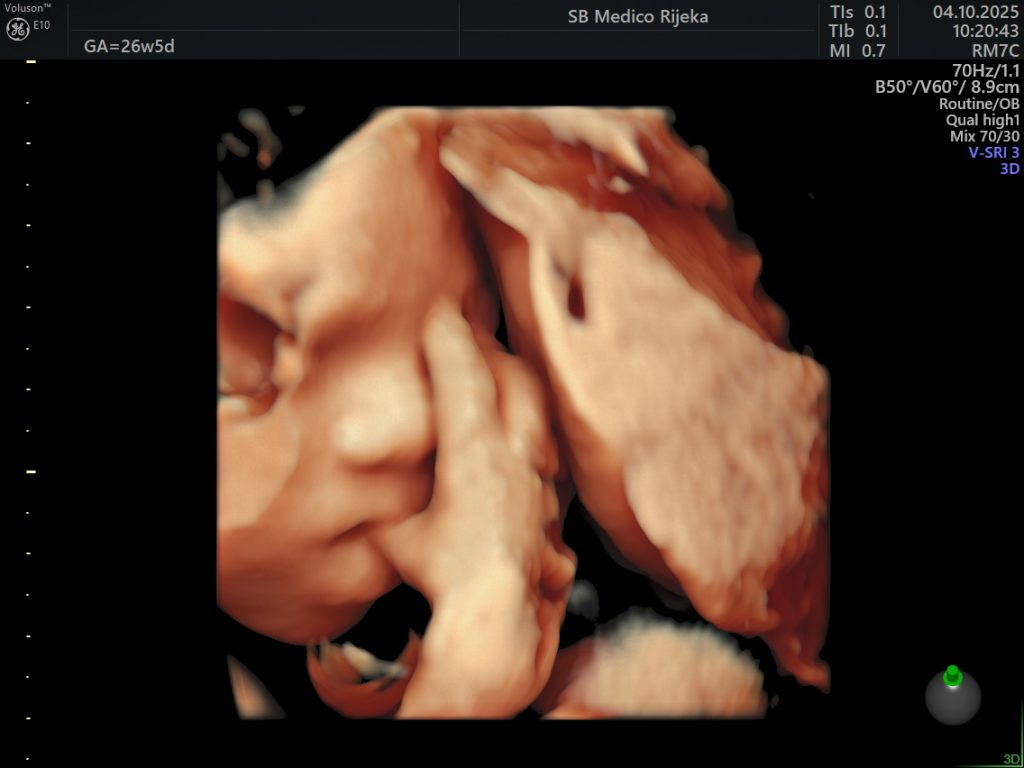

3D/4D ultrazvuk – trenutak koji ostaje zauvijek

Suvremeni 3D/4D ultrazvuk donosi novu dimenziju praćenja trudnoće. Omogućuje detaljniji prikaz razvoja djeteta prilikom svakog pregleda, a budućim roditeljima pruža priliku da na ekranu jasno vide lice svog djeteta, njegove pokrete i geste.

Iako je riječ o dijagnostičkoj metodi koja pomaže liječnicima u procjeni razvoja fetusa, taj pregled često ima i snažnu emocionalnu vrijednost, jer je to trenutak u kojem roditelji prvi put “upoznaju” svoju bebu.

U Medicu se 3D/4D ultrazvuk obavlja na najsuvremenijim uređajima visoke rezolucije koji omogućuju iznimnu jasnoću slike, a stručni tim ginekologa osigurava preciznu analizu i ugodno iskustvo pregleda.

Osim što doprinosi sigurnosti trudnoće, taj pregled mnogim roditeljima ostaje jedna od najljepših uspomena, jer je često to prvi osmijeh, zijevanje ili pokret njihove bebe koji imaju prilike vidjeti.